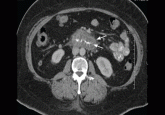

A 46-year-old man with fever, ST-segment elevation

We have all experienced the sudden recognition of an unexpected diagnosis, such as the case of visceral angioedema due to angiotensin-converting...

If a middle-aged woman taking an angiotensin-converting enzyme inhibitor presents with abdominal pain and emesis, the differential diagnosis...